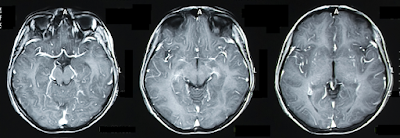

maintenant peut-être en partie une préoccupation du passé car une nouvelle

application d’IA s’est avère tant bien que des médecins à interpréter des

radiographies.

Sans intervention

chirurgicales et à partir de radiographies complexes à échelle de gris, les

médecins peuvent détecter divers maladies, de problèmes cardiaques aux tumeurs

cancéreuses. De former de l’IA à faire la même chose est un des domaines le

plus axé dans la recherche. Des chercheurs de l'Université de Californie ont maintenant

réussi à mettre au point une procédure d’IA capable à détecter des hémorragies cérébrales aussi précisément que des

médecins expérimentés.

Pour réussir il a fallu

une procédure d’apprentissage en profondeur de plus de 4 000 images du cerveau

de patients réels ayant subi une tomodensitométrie.

La technique a ensuite été

testée sur 200 nouvelles images et comparé avec les jugements de 4 radiologues expérimentés.

La procédure d’IA avait une précision supérieure à 2 de ces médecins.